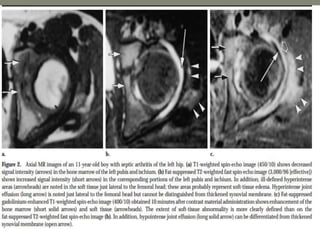

MRI- both tenosynovities and septic arthritis show

T1 hypo T2 /STIR joint effusion

Contrast enhanced image [T1+C]-

Rim of enhancing hypertrophic synovial membrane

differentiated by hypo intense joint effusion

MRI-

1]septic arthritis show signal intensity alteration in the

bone marrow of affected hip joint

2] In transient synovities cases show no such altered

signal entity in bone marrow

T1- poorly defined low signal intesity

T2-/STIR: hyperintese

Contrast study : show enhancment

MRI- both tenosynovitiesand septic arthritis show T1 hypo T2 /STIR joint effusion Contrast enhanced image [T1+C]- Rim of enhancing hypertrophic synovial membrane differentiated by hypo intense joint effusion

• 54.

MRI- 1]septic arthritis showsignal intensity alteration in the bone marrow of affected hip joint 2] In transient synovities cases show no such altered signal entity in bone marrow T1- poorly defined low signal intesity T2-/STIR: hyperintese Contrast study : show enhancment